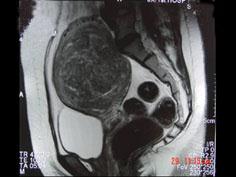

问题 女性,36岁,腹痛,自觉摸到包块,行B超检查提示盆腔内巨大包块,进一步行MRI检查,如图所示,考虑为 ( )

选项 A、卵巢囊肿 B、膀胱憩室 C、子宫腺肌瘤 D、子宫癌 E、子宫肌瘤

答案 C